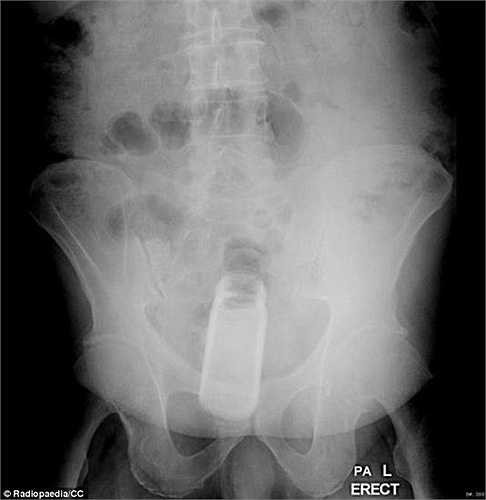

Bệnh nhân này trong khi quan hệ tình dục đã sử dụng đồ chơi tình dục tự chế bằng cách vặn một ống thuốc vitamin Berocca đặt lên đỉnh hộp xịt rồi cho nó vào trực tràng.